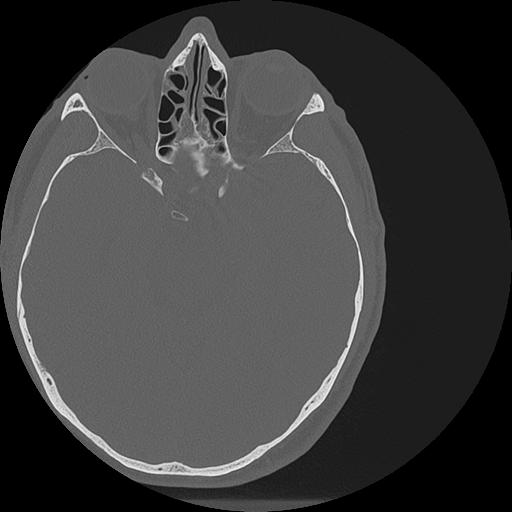

7 HUESO,,Vol,0.5,HUESO,,